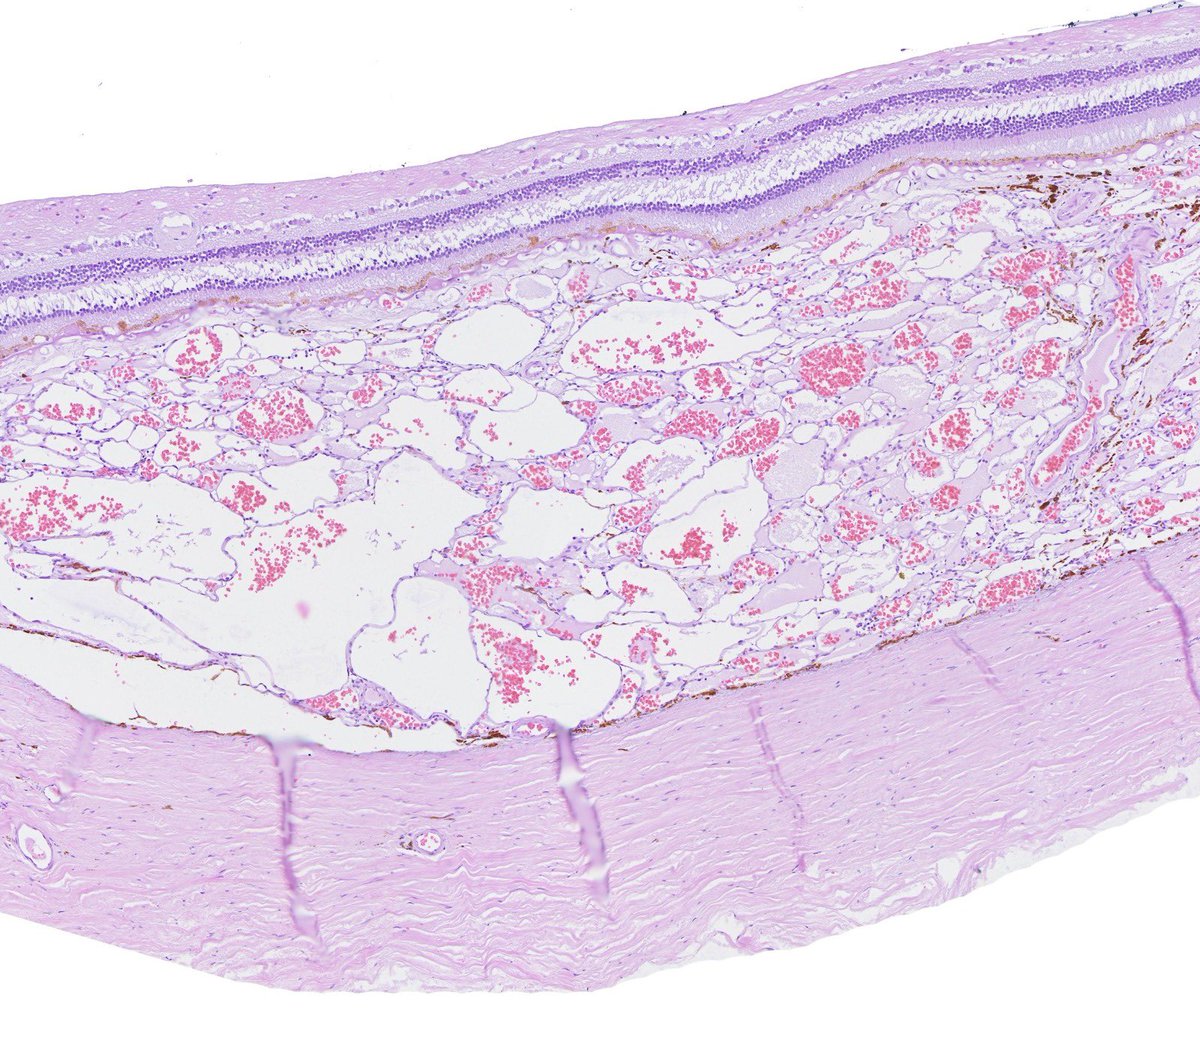

The frozen section